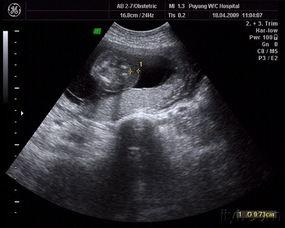

当你怀孕三个半月时,宝宝的成长已经进入了一个新的阶段。这个时候,通过超声波检查,你就可以看到宝宝的小模样了。让我们一起来看看这些珍贵的图片吧!

三、怀孕三个半月胎儿图片:宝宝的性别之谜

怀孕三个半月,很多准妈妈都迫不及待地想知道宝宝的性别。通过超声波检查,我们可以看到宝宝的外生殖器,从而判断宝宝的性别。

1. 男孩:男孩的生殖器在超声波图片中比较容易辨认,通常呈“Y”字形。

2. 女孩:女孩的生殖器在超声波图片中比较难以辨认,但通常呈“V”字形。